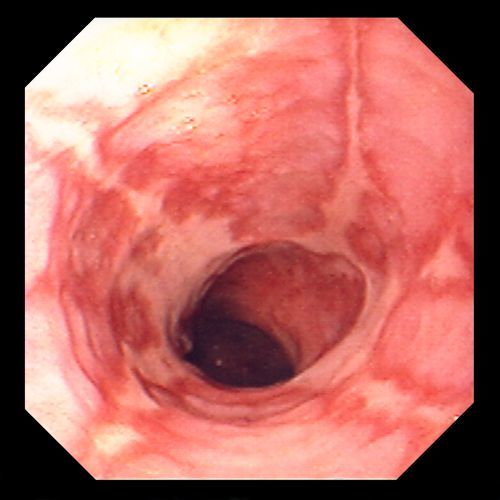

Gross Features of Esophagitis

Hyperemia +/- ulceration